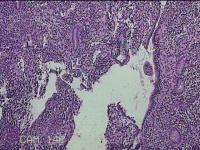

性别

女

年龄

42岁

临床诊断

异常子宫出血

一般病史

阴道不规则流血49天。

标本名称

宫腔组织

大体所见

灰白暗红色不规则碎组织2.5x2x0.8cm一堆。